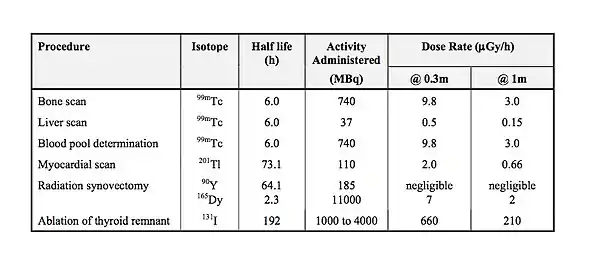

Note that the half-life does not express how long a material will remain radioactive but simply the length of time for its radioactivity to halve. Examples of the half lives of some radioisotopes are given in the following table. Notice that some of these have a relatively short half life. These tend to be the ones used for medical diagnostic purposes because they do not remain radioactive for very long following administration to a patient and hence result in a relatively low radiation dose.